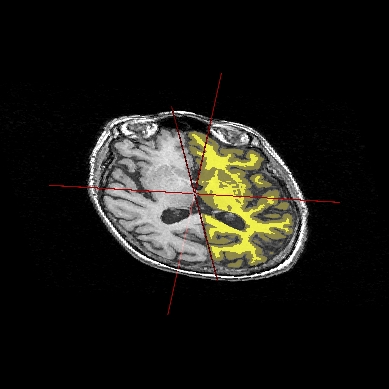

STEP 1: Load the images to merge. Here, we will fusion an anatomy and the brain mask obtained from BrainVISA anatomical pipeline.

STEP 2: Select the two volumes in objects list with Ctrl + left button.

STEP 3: Then click on fusion button

.STEP 4: A new window pop up to select objects order and fusion type (fusion types offered differs according to selected objects, this will be detailled later, in advanced part of the manual).

STEP 5: Click on Ok to create the new Fusion2D object.

STEP 6: Put the Fusion2D object in a window.

STEP 7: If the Fusion2D object is all in black, you must change fusion mode. So right click on Fusion2D object to get its menu. Choose Fusion => Control 2D fusion. This window opens:

Fusion control¶

STEP 8: You can change the mapping mode. The default is Linear: it does a linear combination of the two volumes. The Geometric mode does RGB channels multiplication. For linear fusions, you can set objects transparency with the cursor Mixing rate.

STEP 9: By default, the 2 volumes will have the same palette. To change at least one, do Right clik menu on a volume => Color => Palette.

Example of a linear fusion between two 3D volumes¶